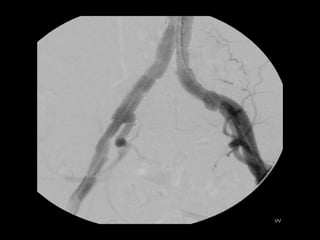

Iliac aneurysmIliac aneurysm

http://www.perfuse.netVascular surgery @ Tallaght